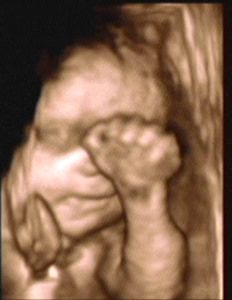

3D/4D SONOGRAPHY 18-24 WEEKS

- Normal Sonography is 2 dimensional. In 3 dimensional Sonography the information is obtained simultaneously in 3 planes (X, Y & Z).

- Highly sophisticated software reconstructs this information into a distinct 3D image.

- From a continuous 3D acquisition you get a live action view. It is known as 4D where 4th dimension is time.

- Improved identification of suspected or detected anomalies.

- More accurate identification of the extent & size of anomalies.

- Improved maternal -fetal bonding.